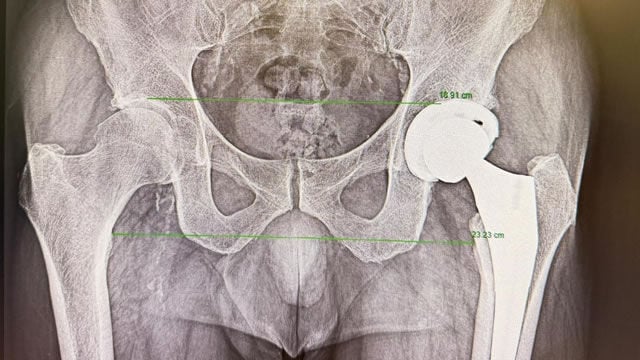

El reemplazo de cadera es una de las cirugías ortopédicas más habituales para tratar patologías como la artrosis avanzada, fracturas o deformidades que generan dolor persistente y limitación funcional. Su objetivo es aliviar el dolor y recuperar la movilidad, mejorando de forma notable la calidad de vida del paciente.

La llamada vía anterior en la prótesis de cadera no es una técnica nueva, aunque en los últimos años ha ganado popularidad. A diferencia de otros abordajes, permite acceder a la articulación entre planos musculares, sin necesidad de cortar músculos, lo que se traduce en un postoperatorio inmediato más rápido.

“La gran ventaja de la vía anterior es que el paciente tiene menos dolor en los primeros momentos tras la cirugía y puede iniciar antes la movilización”, explica el Dr. Martín Buenadicha. A medio plazo, los resultados funcionales tienden a equipararse con otras vías, pero esta recuperación inicial más ágil resulta especialmente relevante cuando se plantea un alta precoz.

Además, esta menor agresión muscular facilita un inicio más rápido de la deambulación y la fisioterapia, lo que contribuye a una recuperación funcional temprana.